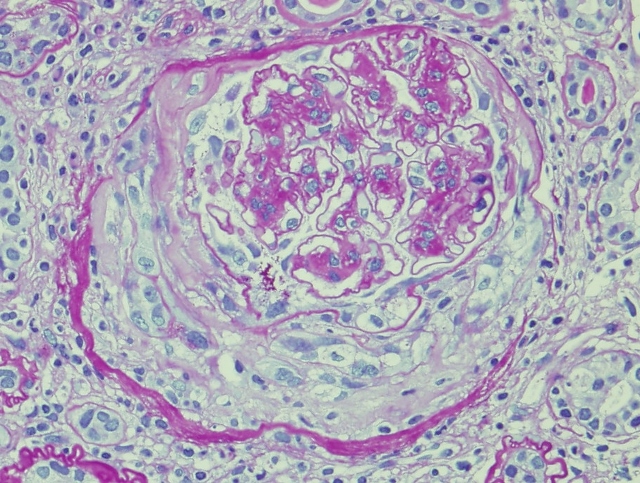

But what if it is a crescent of non-immune etiology? Also described as superimposed lesions of collapsing glomerulopathy (CG) on DN, it is characterized by proliferation of parietal epithelial cells (PECs). These ‘crescents’ do not show inflammatory cells and GBM has continuity, without any breaks and there is no fibrin in the Bowman space. CG lesions in DN are associated with an increased rate of progression of disease with earlier onset of ESRD. PEC markers like Claudin-1 show strong positivity in Bowman space in these lesions. In fact the cells in Bowman`s space in these crescents show double positivity with Claudin-1 and Nephrin (a visceral epithelial cell marker) in one study. This indicates de-differentiation of PECs into podocytes, forming cross bridges across the urinary space with the PECs trying to replace the latter as podocytopenia is a prominent feature in DN.

There are no definite treatment recommendations for these lesions in DN. Based on few case reports available, aggressive control of diabetes, hypertension and use of ACEI/ARB`s might help to some extent. But the overall prognosis is grim. This highlights the need for careful assessment of such patients. Diabetic patients may have true crescentic , but not all ‘crescents’ in diabetes are crescentic glomerulonephritis!